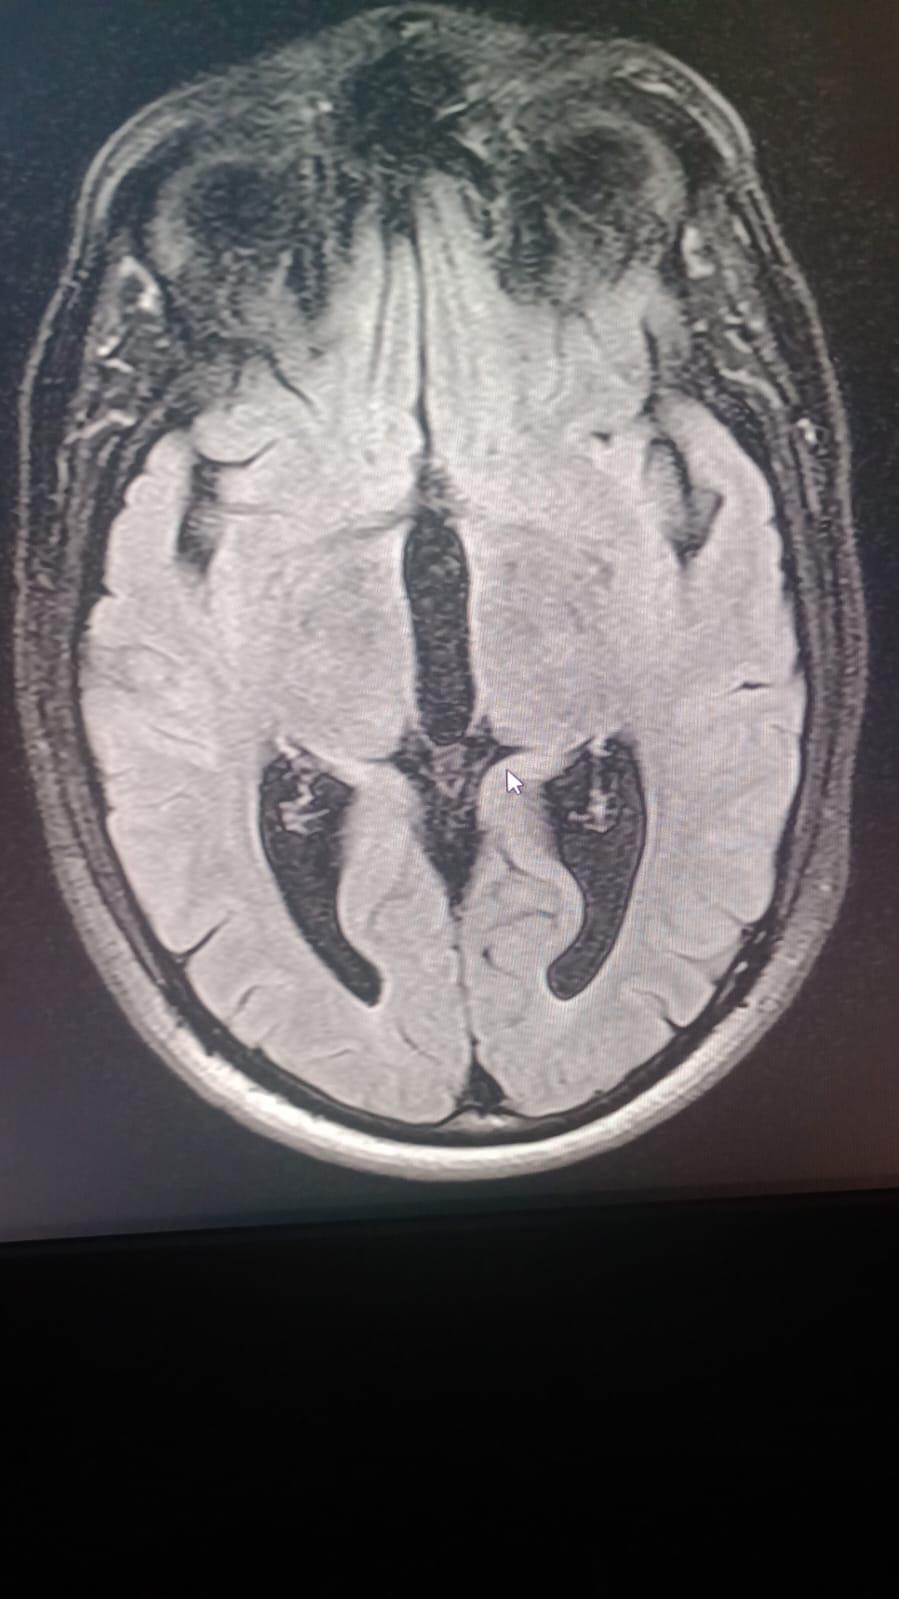

Our dear Cesar Eduardo Rodríguez Ortiz has been fighting seizures since he was just two years old, after suffering a head injury as a baby. Despite years of struggle, his strength and spirit have never faded.

On October 17, 2025, Cesar underwent a major brain surgery to help control his severe epilepsy. By God’s grace, the surgery went well, and he is now beginning his road to recovery.